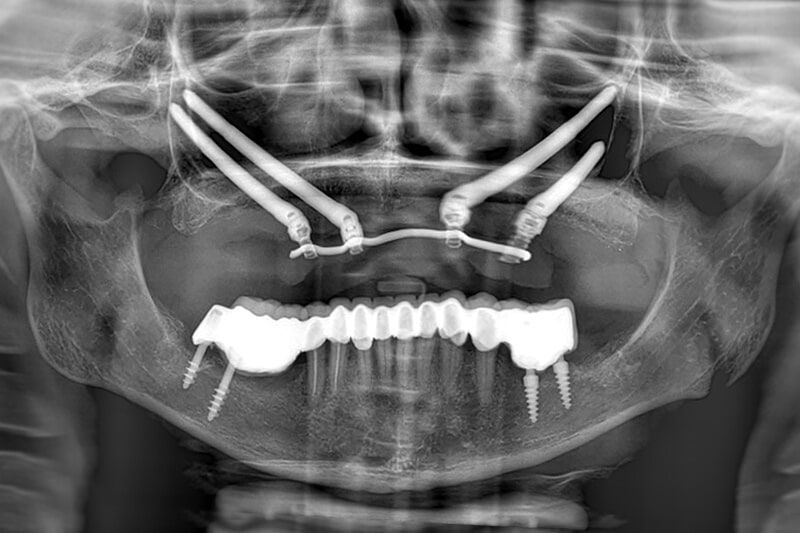

PATIENT WITH ATROPHY OF THE UPPER JAWBONE

Four zygomatic implants were placed under general anaesthesia with a prosthesis completely fixed to the implants in less than 24 hours.